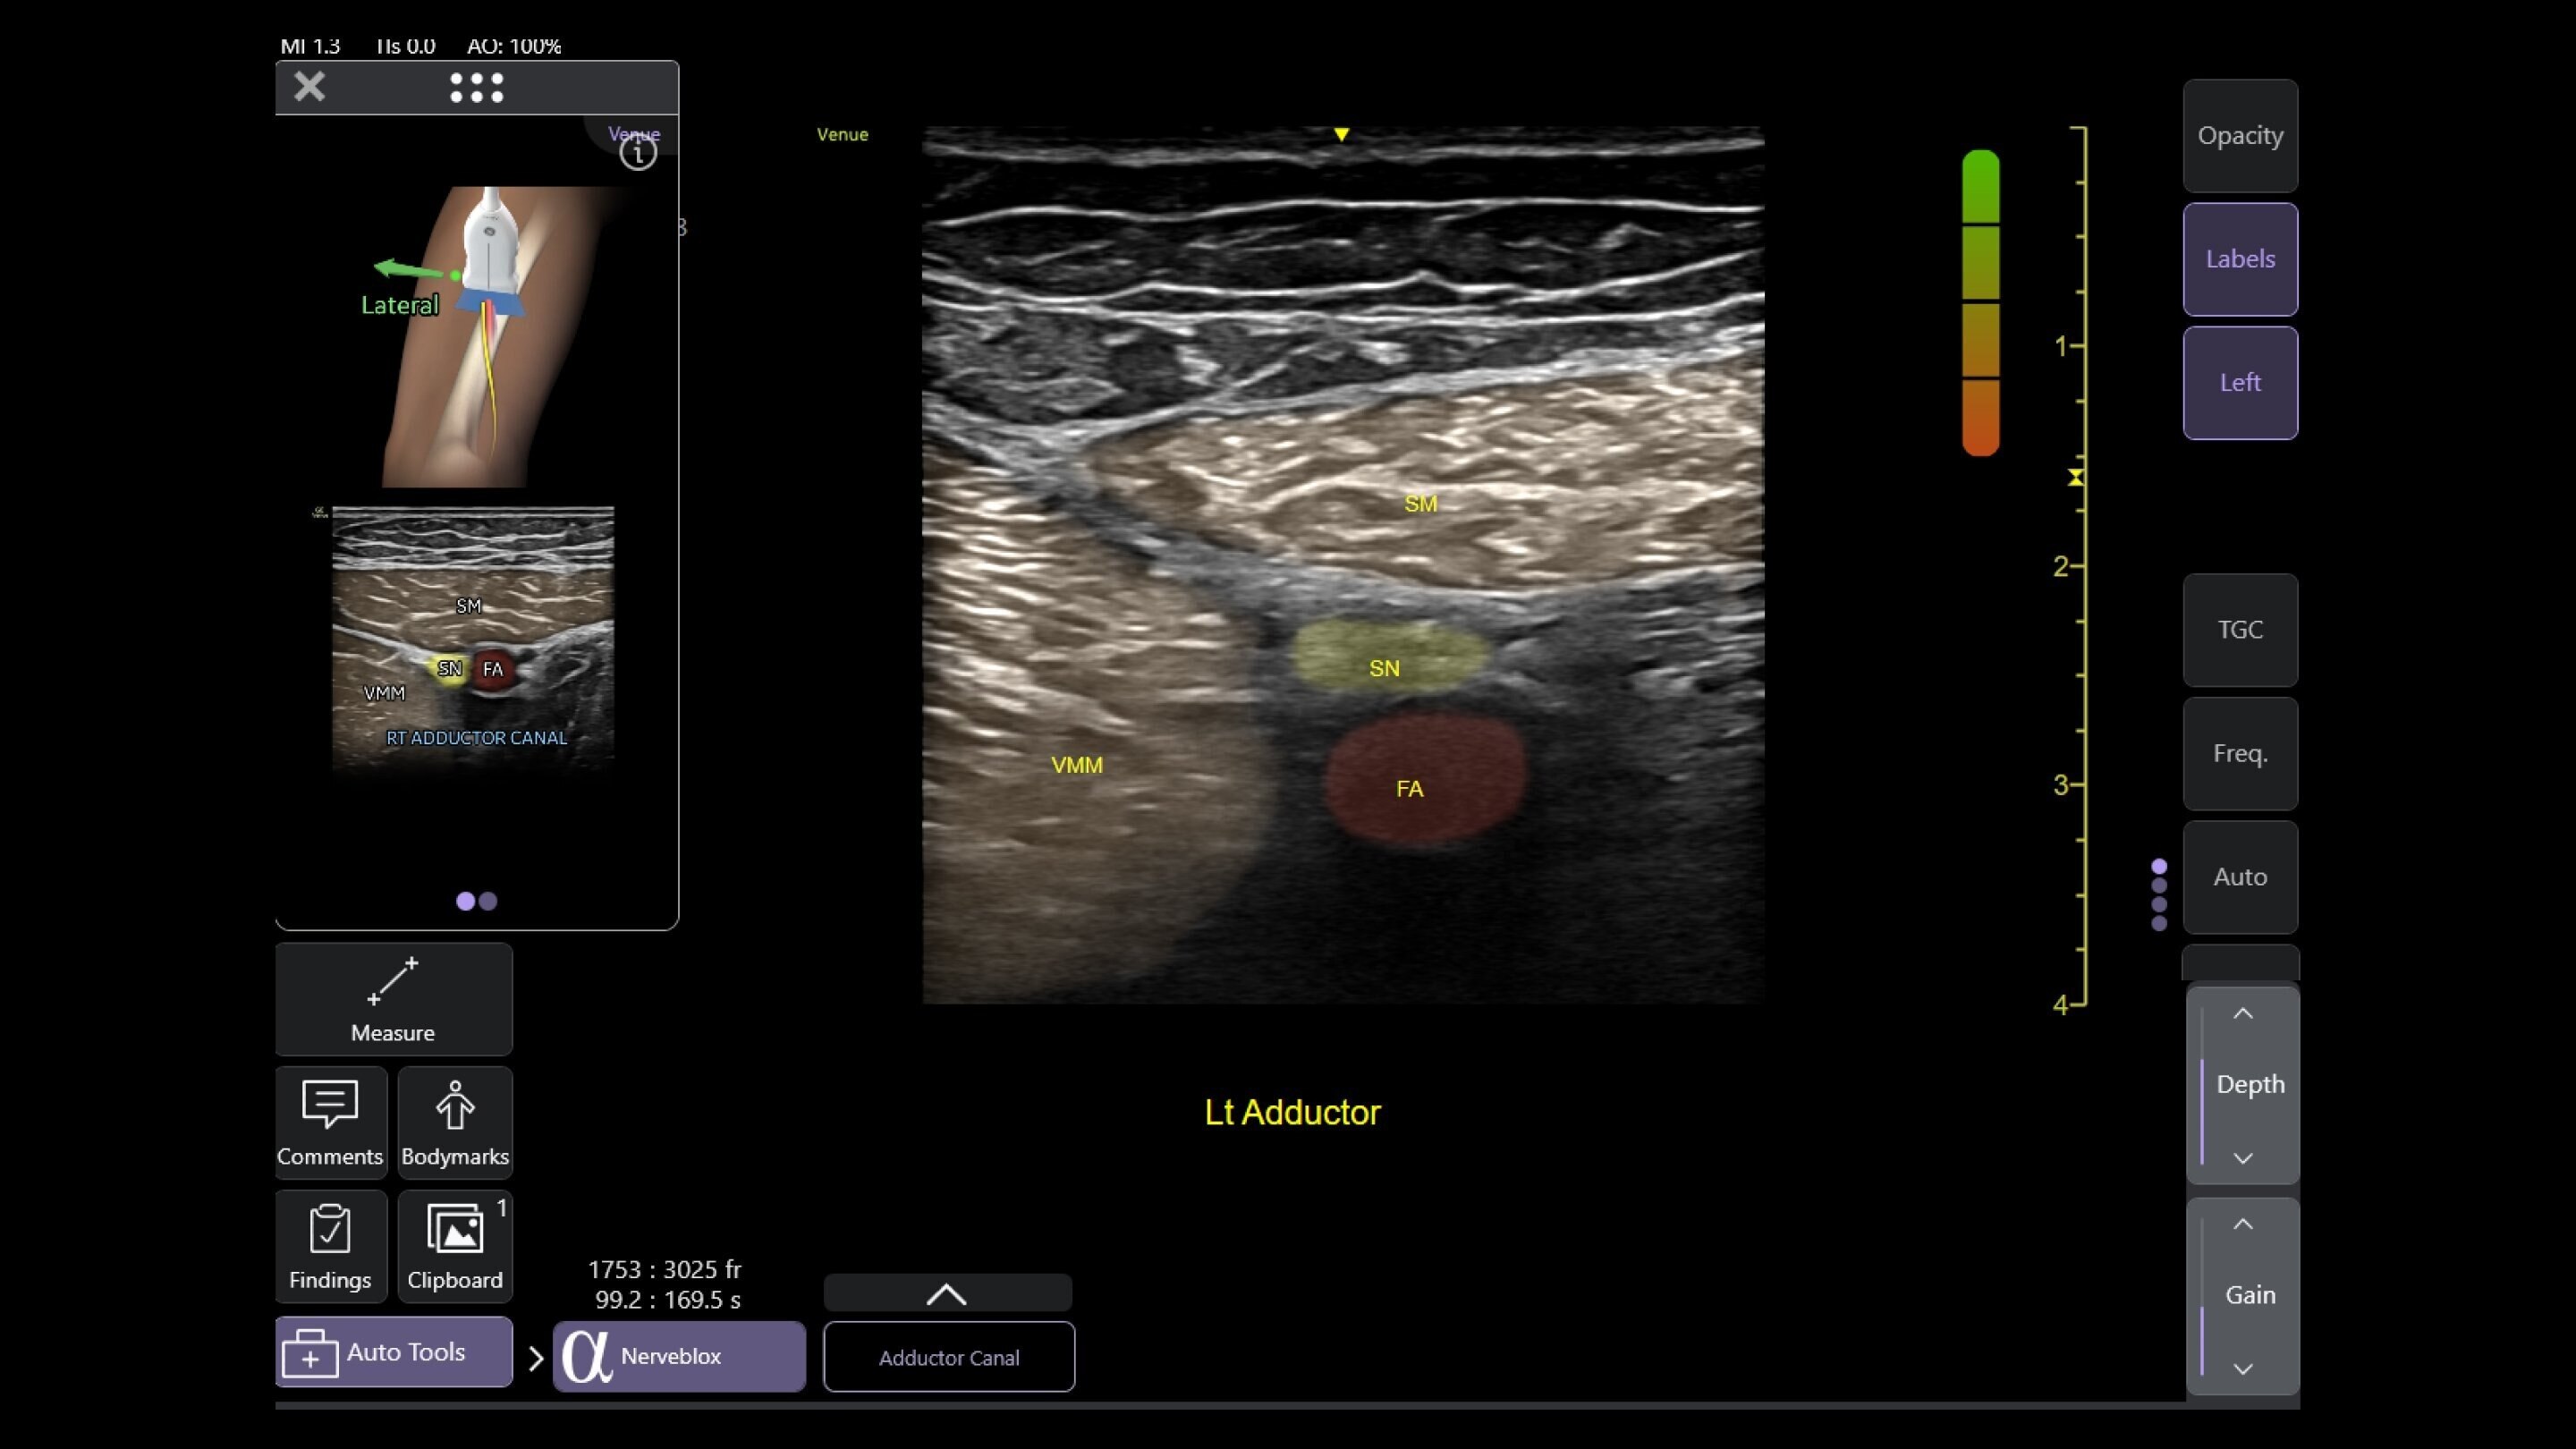

Venue Sprint™ gives you the uncompromised image quality and smart workflow of Venue™ family systems along with the freedom and maximum portability of wireless probes. This all-in-one, entry-level solution combines wireless connectivity with a small, streamlined console. It features Venue family software, to give you access to the AI tools you need, to simplify advanced exams whenever and wherever care is needed.

Musculoskeletal (MSK)

A curved array on one side and linear array on the other of the dual wireless probe enables clear assessment of deep and shallow anatomy without switching probes.